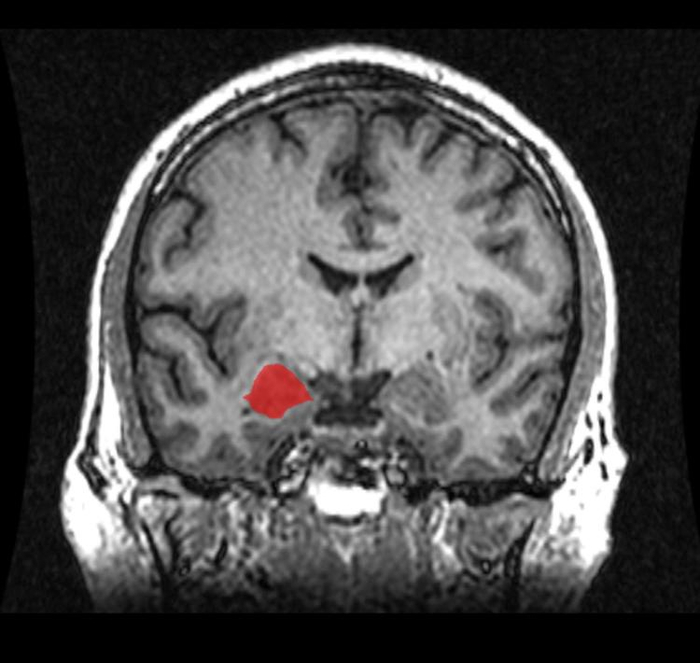

科学家研究了一群有低放射水平的 MOAO 人,发现大脑结构的确和正常人的有些不同,比如他们大脑的杏仁核里的灰质体积、扣带回会比正常人少、控制情感的前扣带回也没有一般人发达,但是目前还没有正式的研究来说明这些异常的大脑结构和暴力行为和反社会行为有关系。

红色部分为杏仁核,里面有灰质,MOAO 放射水平低的人灰质体积会比正常人少。